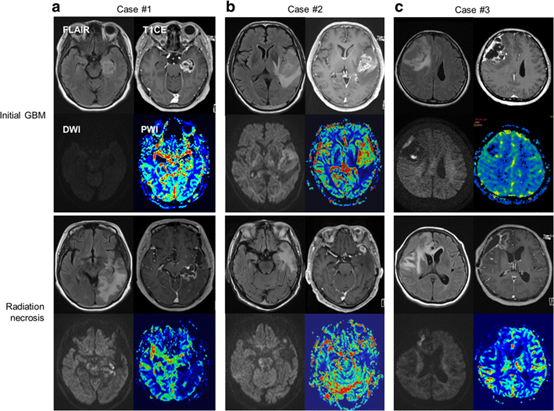

Hình 5: Đặc điểm MRI của u nguyên bào thần kinh đệm (GBM- Glioblastoma) và hoại tử do xạ trị trong từng trường hợp.

a. Trường hợp 1 có GBM và hoại tử do xạ trị sau đó ở thùy thái dương trái.

b. Trường hợp 2 có GBM và hoại tử do xạ trị ở thùy thái dương trái.

c. Trường hợp 3 có GBM và hoại tử do xạ trị ở thùy trán phải.

Chụp cộng hưởng từ tưới máu bao gồm một nhóm các kỹ thuật cộng hưởng từ có thể đánh giá định lượng các biến số huyết động học não khác nhau như thể tích máu não tương đối (rCBV- relative cerebral blood volume), lưu lượng máu não (CBF- Cerebral blood flow), tính thấm mao mạch (Ktrans), thời gian vận chuyển trung bình (MTT- Mean transit time ) và các biến số khác. rCBV là một dấu hiệu hình ảnh của quá trình tân sinh mạch máu và giảm trong hoại tử não do bức xạ. Tỷ lệ các giá trị CBV thu được từ tổn thương mục tiêu và mô bình thường ở bên đối diện có thể được sử dụng để ước tính mật độ vi mạch mô và phân biệt giữa hoại tử não do bức xạ và sự tiến triển của khối u. Nhìn chung, các khối u tái phát được phát hiện có tỷ lệ rCBV từ 2,5 trở lên, trong khi tỷ lệ rCBV < 0,6 có liên quan đến hoại tử não do bức xạ. Tỷ lệ rCBV là 2,1 được phát hiện có độ nhạy 90% và độ đặc hiệu 80%.